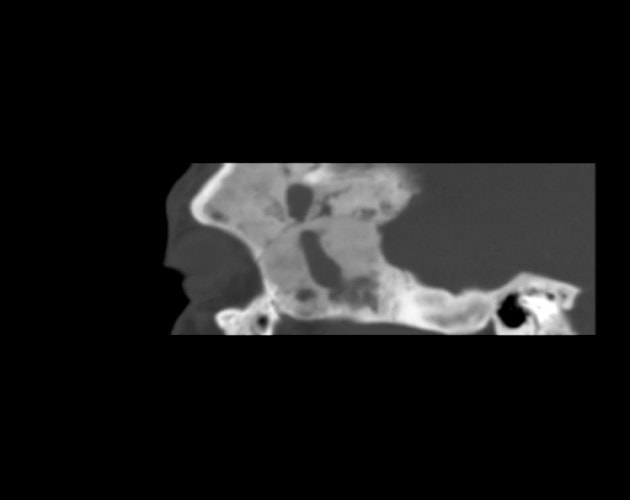

Bone Lesions of the Orbit: CT scan provides the best delineation of bony lesions causing proptosis.

Primary Bony Lesions: Osteomas, osteogenic sarcoma, and fibrous dysplasia.

Secondary Bony Lesions: Metastases from prostate, thyroid, lung, breast, kidney, and the non-metastatic eosinophilic granuloma, otherwise known as histiocytosis X spectrum.

- The initial test recommended in a suspected case fibrous dysplasia is X-ray which shows characteristic mottling and sclerotic changes with a “ground-glass” appearance. Computed Tomography clearly shows cystic and sclerotic lesions with smooth cortical margins and no soft tissue involvement. MRI shows low to isointense lesions on T1 and T2-weighted images, and demonstrates moderate enhancement with gadolinium.